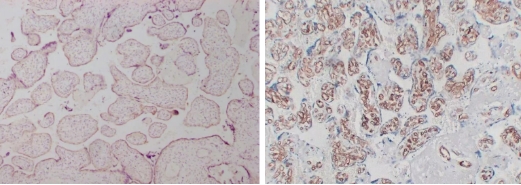

Typical example: Staining of paraffin-embedded human breast cancer tissue sections with different HER2 antibodies:

Left panel: Strong membranous positivity in cancer cells;

Right panel: Weak membranous positivity in cancer cells, indicating insufficient staining intensity of the antibody.

Common problem: Insufficient staining intensity can result in weak positivity in detection results.

Recommendation for Resolution: Appropriately adjust the antibody dilution ratio, or select antibodies with high staining intensity and high affinity.